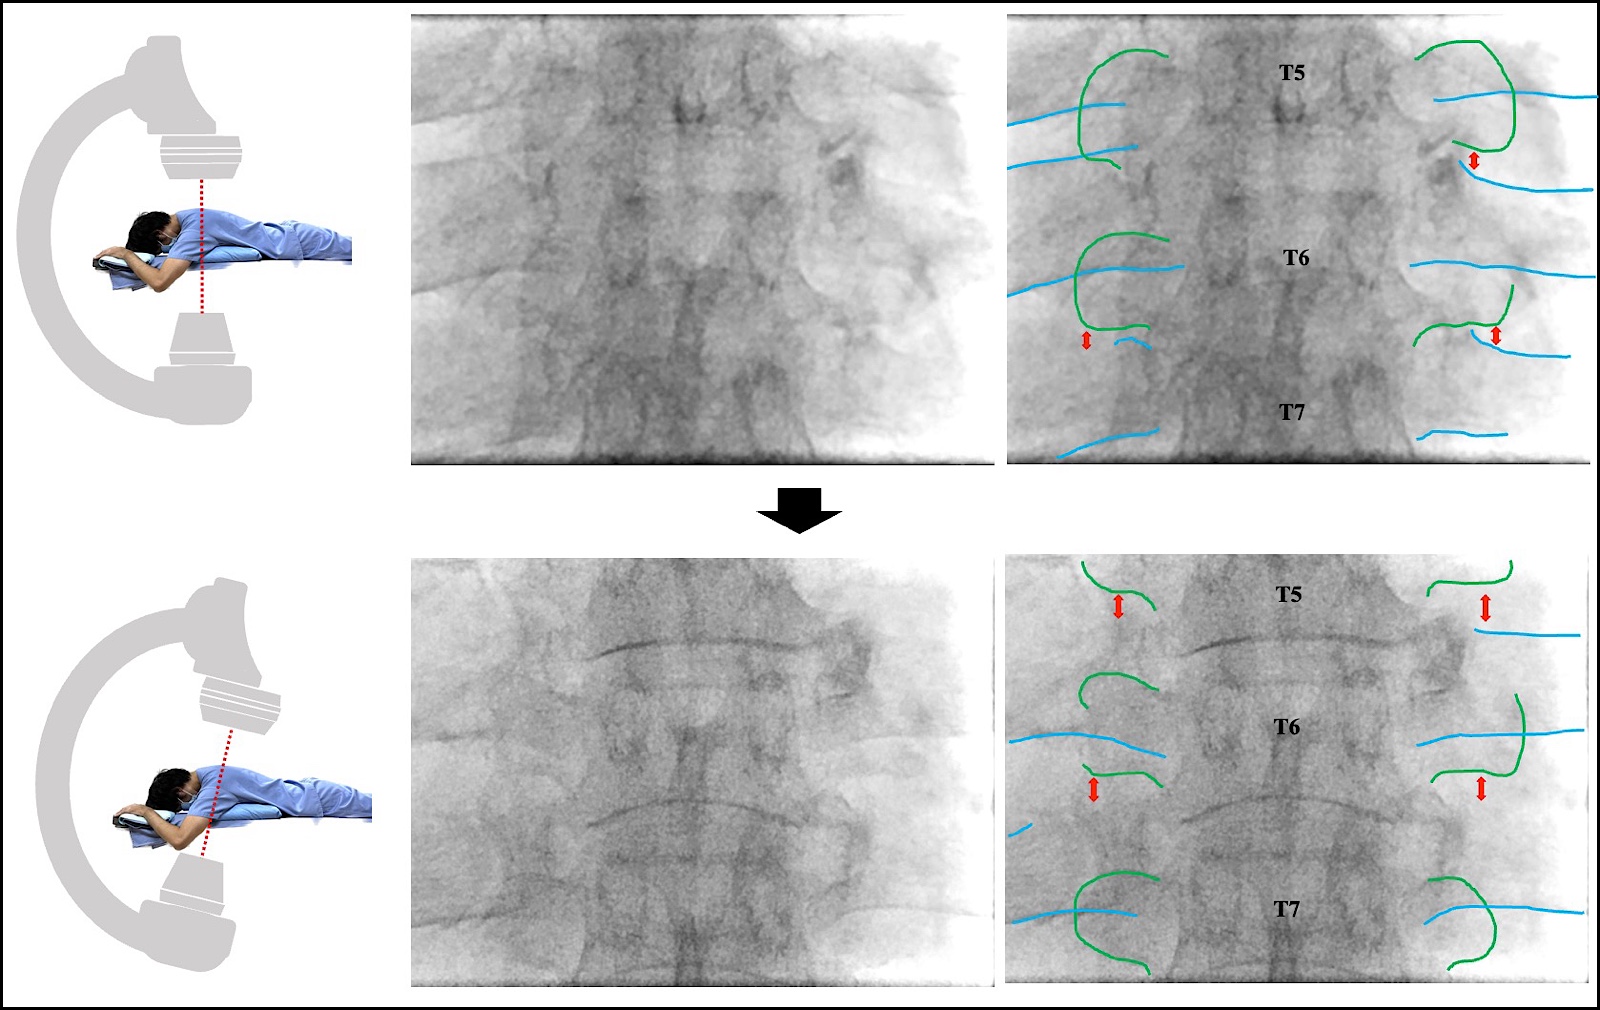

How to Match Body Position and Fluoroscopy

A pillow is placed under the patient’s upper abdomen, and the patient is positioned prone, creating a natural arch with the mid-thoracic vertebra as the apex (Figure 2).

The right-left angle is adjusted so that the spinous process is visible bilaterally in the center of the pedicles under the posterior fluoroscopic view.

As described in the anatomy section, in the posterior view, the nerve root emerging from the intervertebral foramen into the intercostal space appears to be covered by the transverse process. The cranial-caudal angle is adjusted such that the inferior margin of the transverse process and the edge of the inferior articular process are visible in the intercostal space. The nerve root is located on the ventral-caudal side.

In the upper thoracic vertebrae, when adjusting the fluoroscope cranially and caudally in the mid-thoracic vertebrae, the nerve root is often visible (Figures 3a and 3b). In the lower thoracic vertebrae, the anterior curvature of the thoracolumbar junction usually allows for visibility of the inferior margin of the transverse process. In cases of kyphosis or scoliosis, further axis adjustments are required.